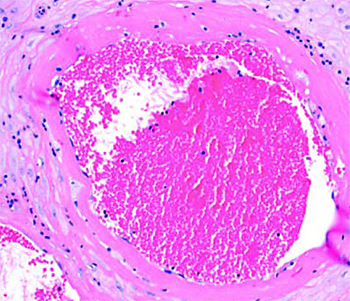

Тромбоз межворсинчатого пространства (см. рис. 4). В сосудах формируются слоистые тромбы, оттесняя на периферию ворсины, которые перестают участвовать в газообмене.

Иван Сахаров обратил внимание, что изменения настолько яркие, что видны на макроскопическом уровне. Если в норме плацентарная ткань рыхлая, насыщенного красного цвета и напоминает пропитанную кровью губку, то при тромбозе становится желтовато-серой, очень плотной и сухой. В ней имеются заполненные кровью участки — это кровоизлияния и формирующиеся тромбы.

Лимфогистиоцитарный виллит, тромбоз (см. рис. 6, 7).

В межворсинчатом пространстве видны скопления воспалительного инфильтрата, тромбоз сосудов ворсин, нарушения созревания ворсинчатого хориона.

«Стереотипная реакция плаценты на повреждение — это нарушение созревания. Как по литературным данным, так и на собственном опыте мы с этим сталкивались при подтвержденном COVID-19. В отличие от зрелой плацентарной ткани видна очень рыхлая строма. При выраженном лимфогистиоцитарном виллите, как правило, наблюдается тромбоз сосудов — и крупных, и капилляров».